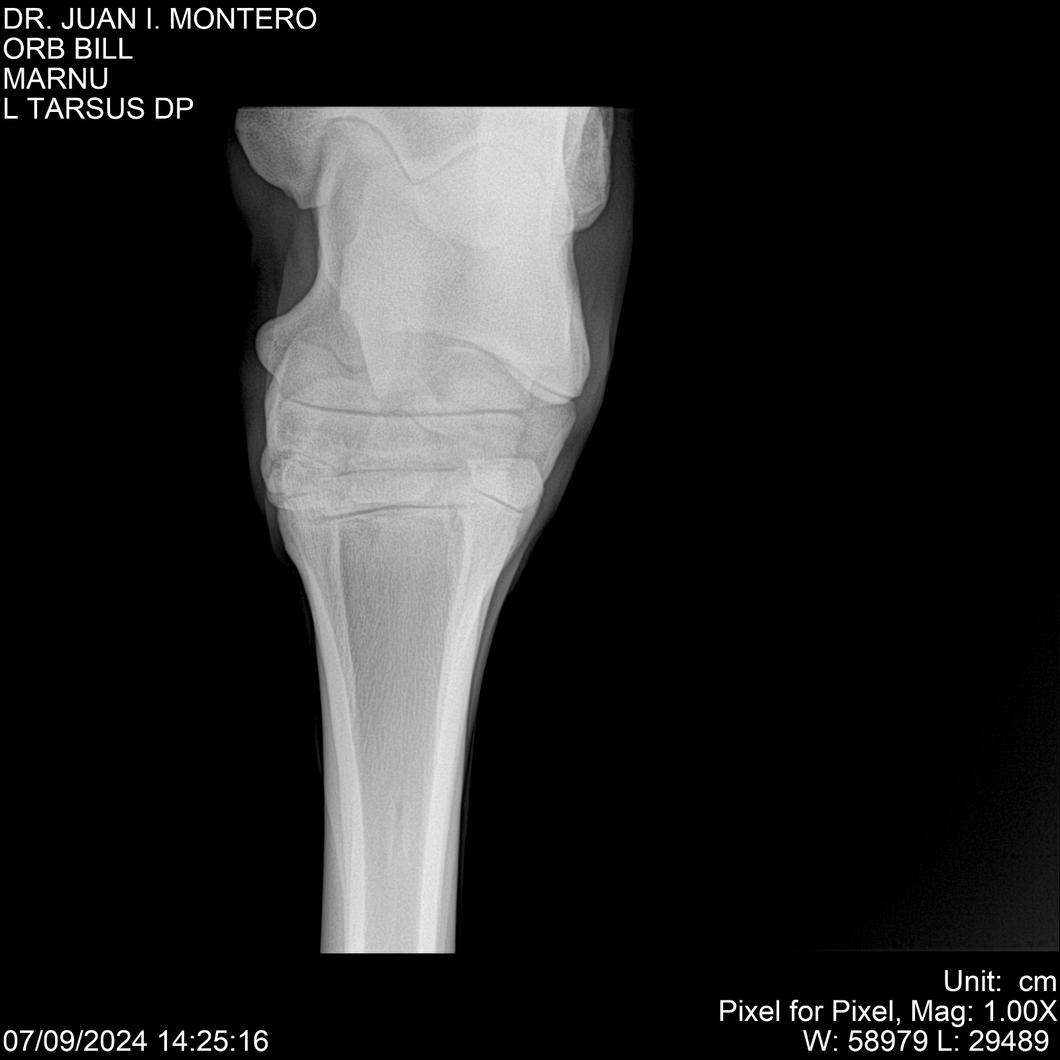

LOTE 7, ORB BILL 🔥 🔥 🔥 Lote Anterior Volver al remate Lote Siguiente Ficha Contacto Montevideo - Ficha del Lote Identificador: #282523 Categoría: Yeguarizos Montevideo - 83 Visualizaciones ClicData Contacto Empresa: Abelenda N. R., Walter Hugo Nombre*: Teléfono* : E-mail* : Mensaje Enviar Registrese gratis Este contenido Exclusivo está disponible sólo para usuarios registrados Ingresar